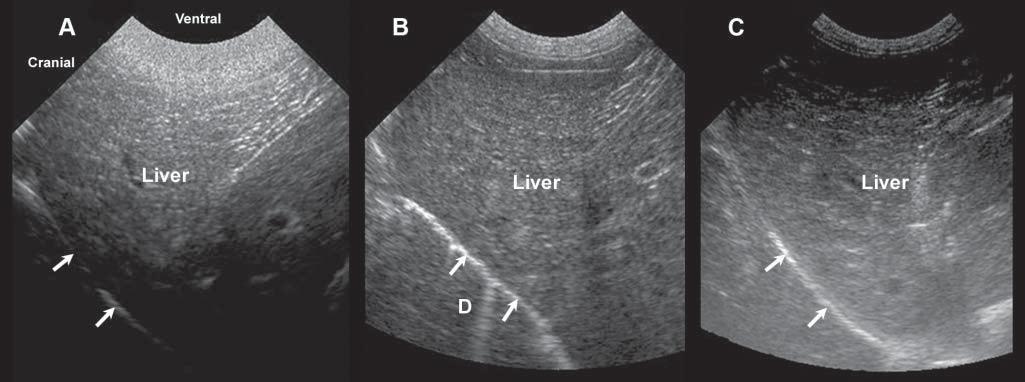

Figure1.8. Gainsetting. Becauseoftheattenuationoftheultrasoundbeamasittravelsthroughsofttissues,theamplification ofechoesreceivedmustbeadjustedaccordingtotissuetypeanddepth.Thismodulationcanbemadeusingtimegaincompensationbarsorfar/near/generalgainknobs.Thesethreeimagesshowthevariationinechogenicityofanormalliverwith excessiveneargainandinsufficientfargain (A),well-adjustednearandfargains (B),andinsufficientneargainandexcessive fargain (C). D,diaphragminterface.

The gain determinesthelevelofamplificationof echoestocompensatefortheirattenuationintissues, increasingthebrightnessofcorrespondingpixelson thescreen.Itcanbeadjustedgenerally,ormodulated specificallyindepth(Figure1.8).Timegaincompensation(TGC)isadjustedthroughslidingknobs, reducingsuperficialamplificationorincreasingdepth amplification,forinstance.Asultrasoundattenuation willvaryfromoneanimaltoanotherandfromone abdominalregiontoanother,dependingontheacousticcharacteristicsofnormalandabnormaltissues, boththegeneralgainandTGCwillhavetobeadjusted duringtheexamination.